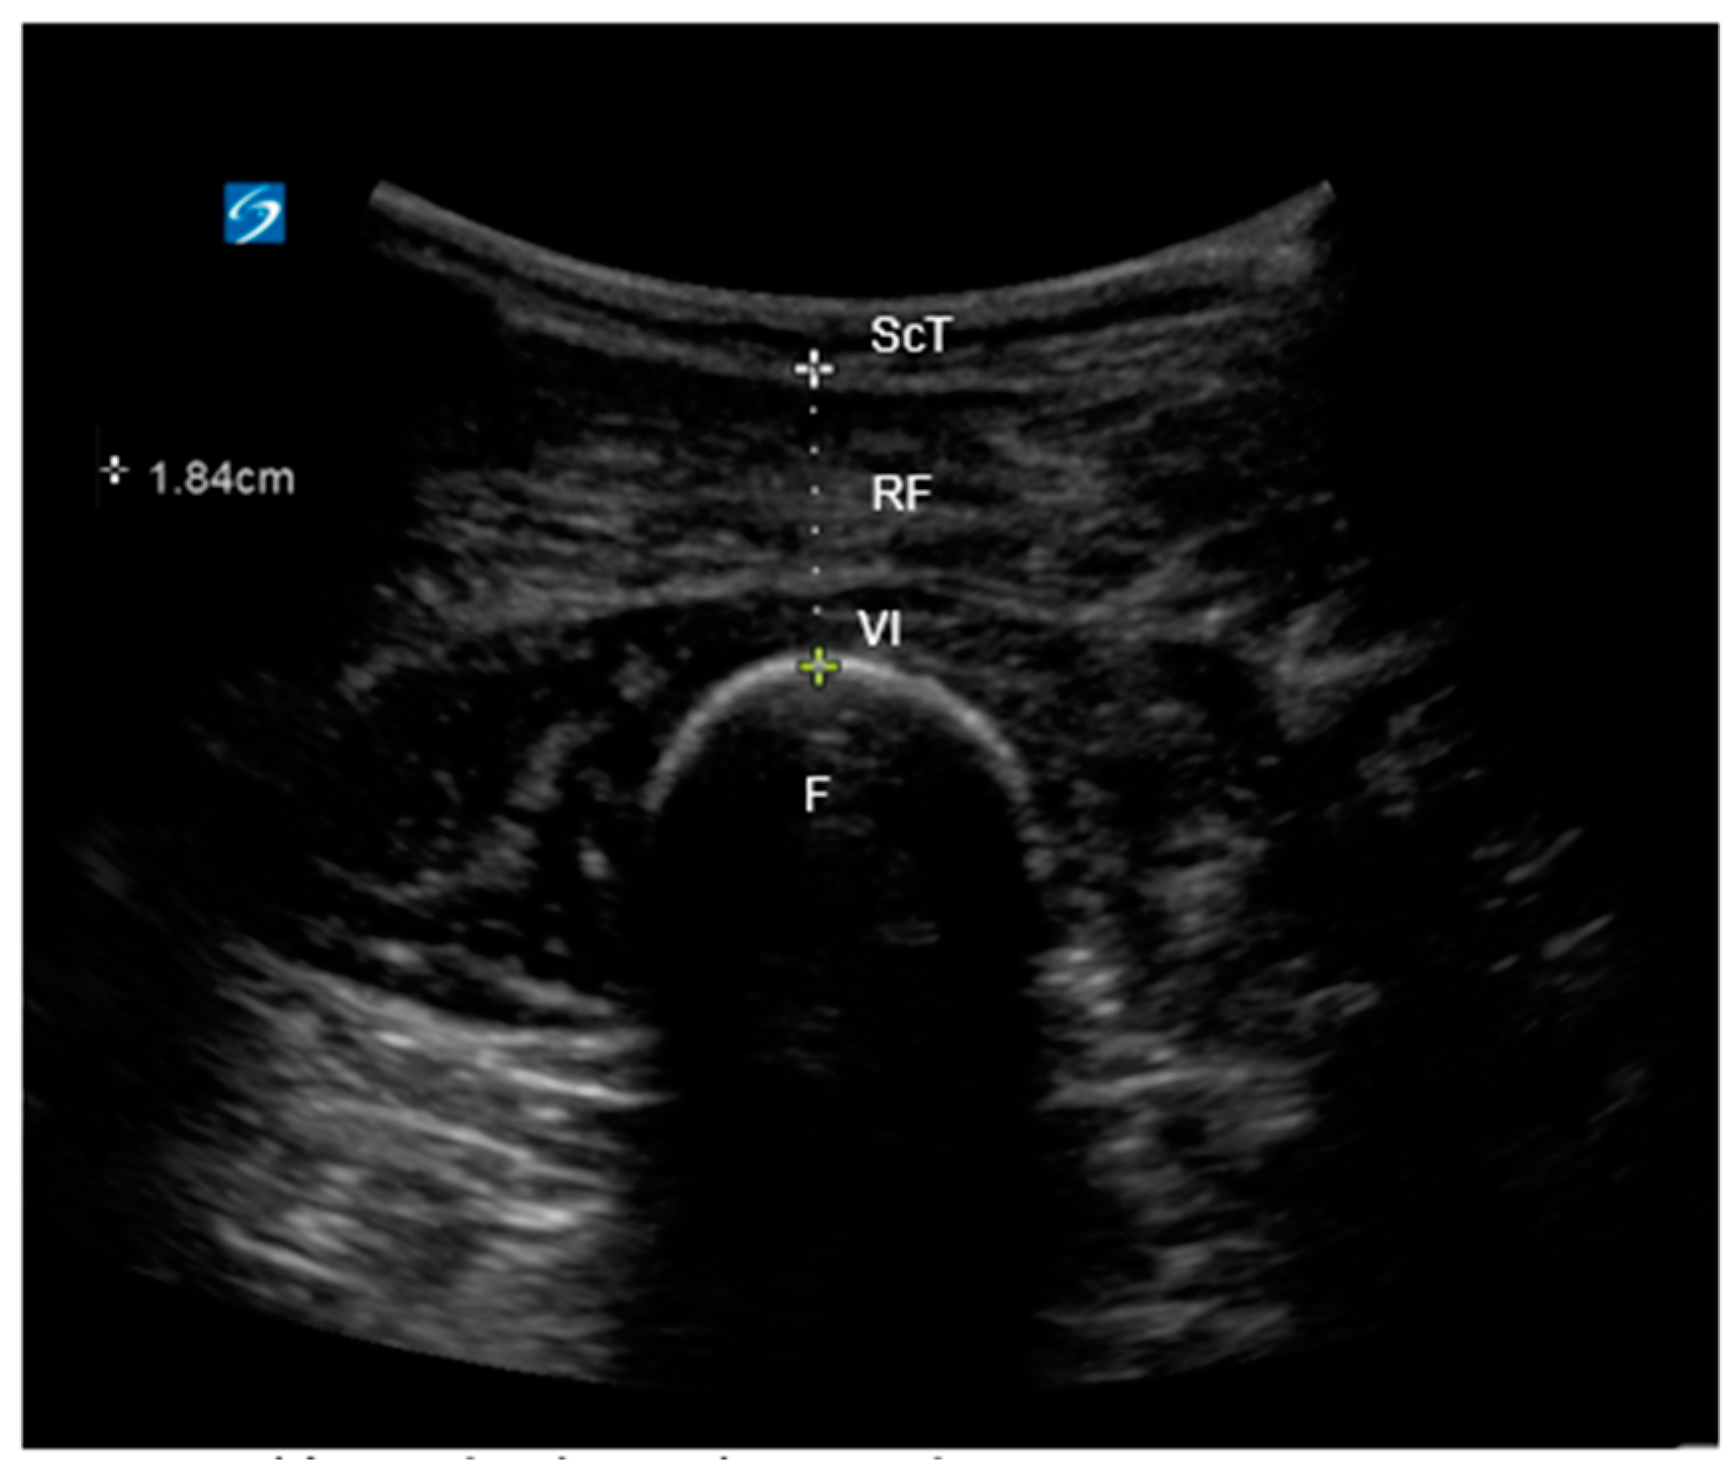

2.4.2. Ultrasound Image Acquisition and Measurement of Quadriceps Depth